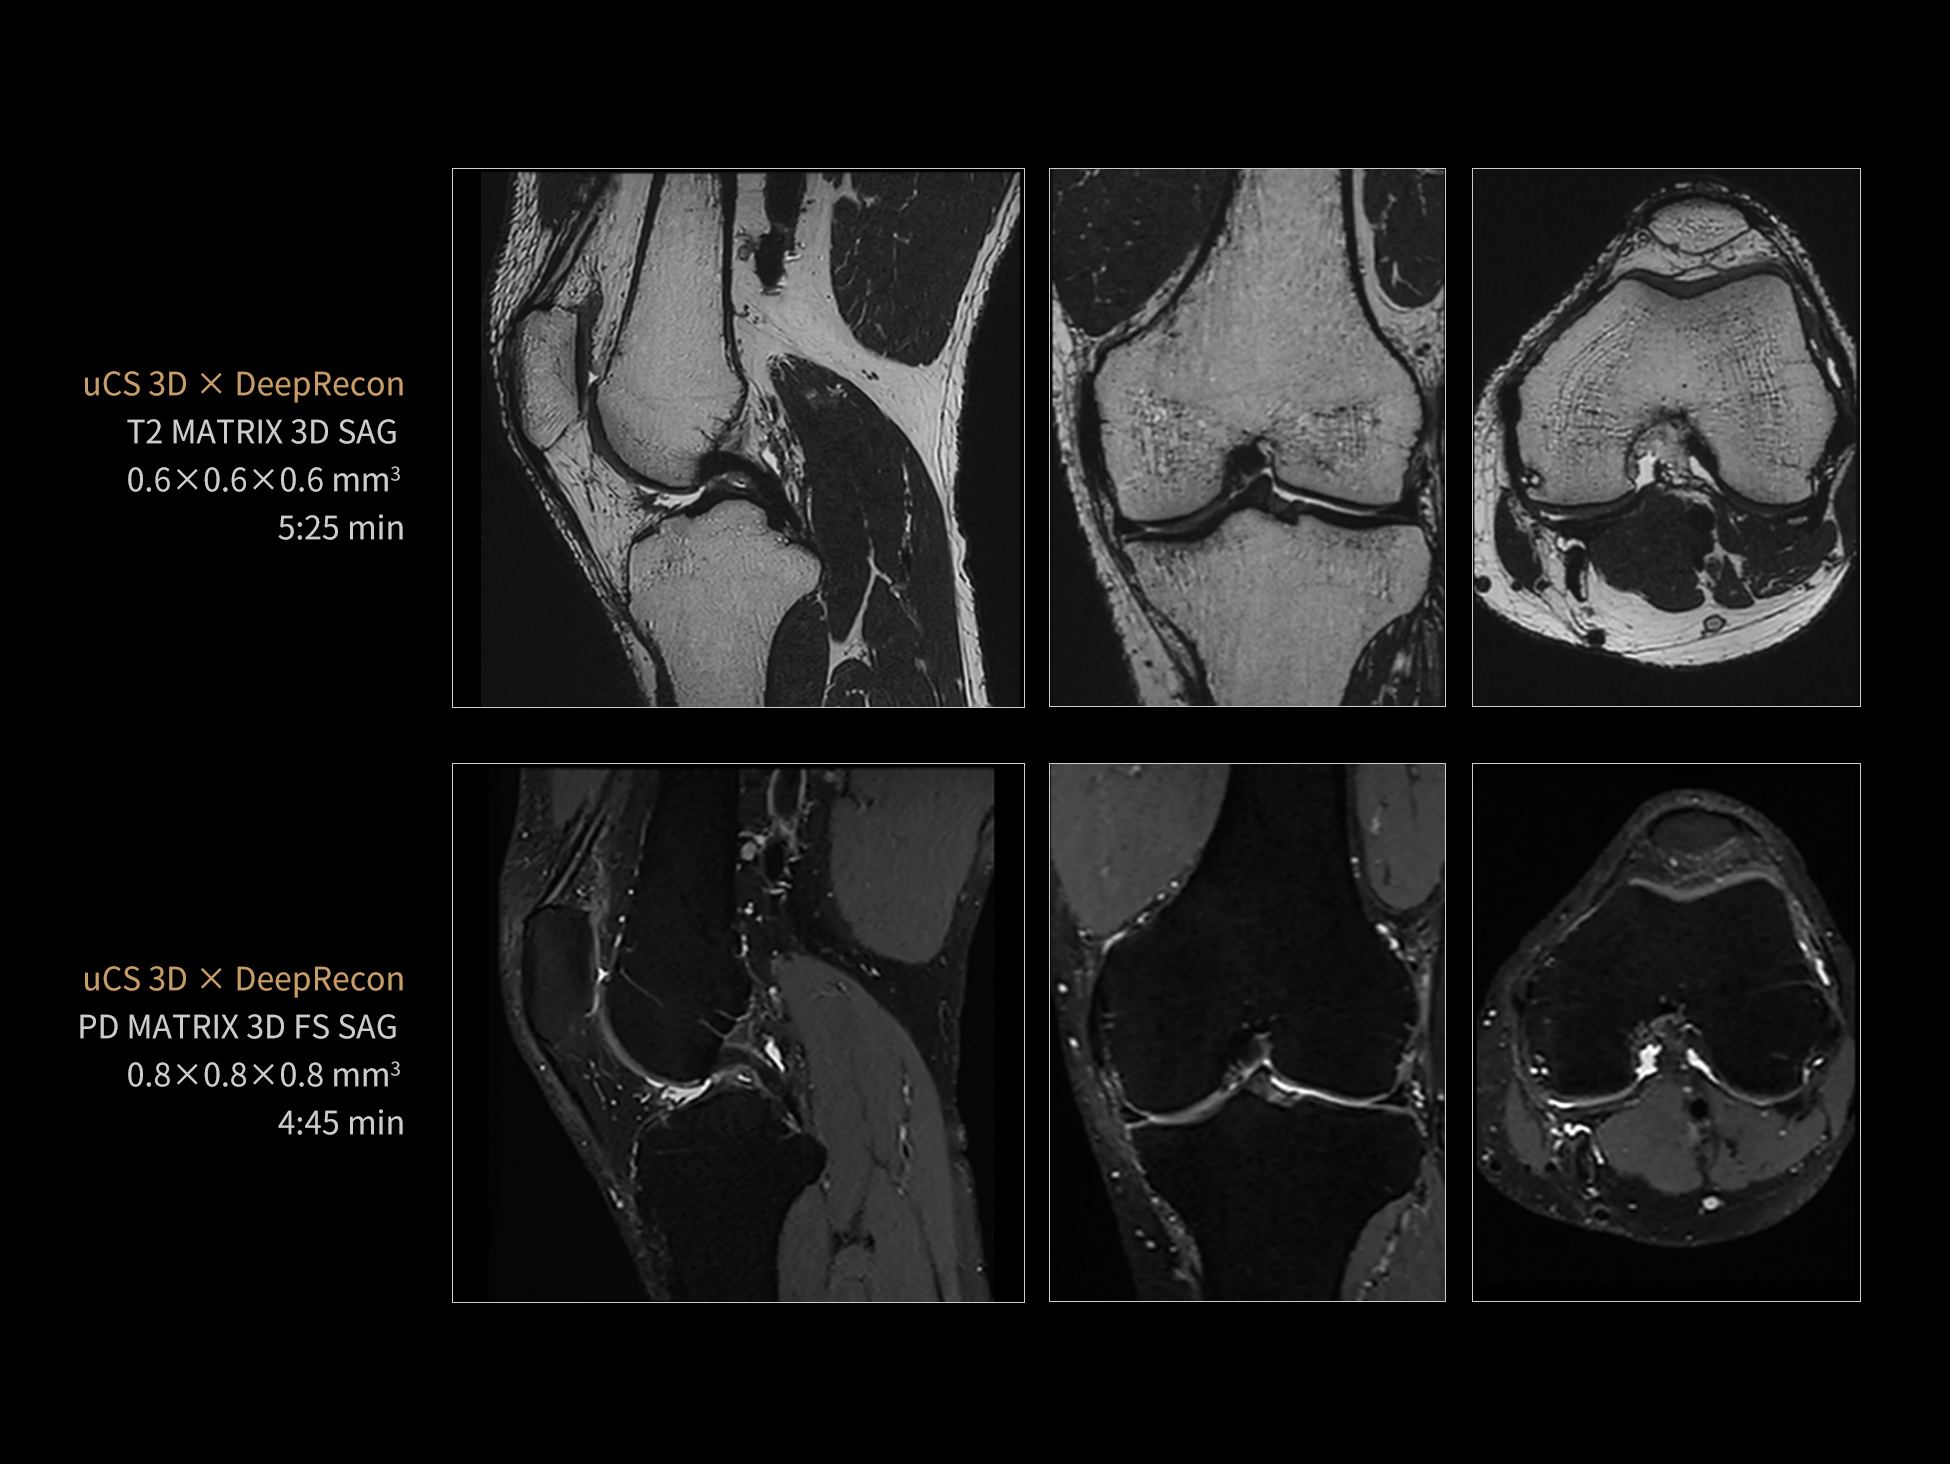

The state-of-the-art uCS technology, featuring high-speed acquisition. With an extensive array of imaging sequences (including 3D and 2D)—it effectively addresses diverse clinical applications across all body parts.

Orthopedics

uCS 3D acquires continuous image data in an extremely short amount of time through a single scan. It allows for the reconstruction of images on any desired plane, including transverse, sagittal, coronal, and any oblique planes. uCS 3D enables more accurate identification of fine structures and detection of lesions, providing confidence in diagnosis.